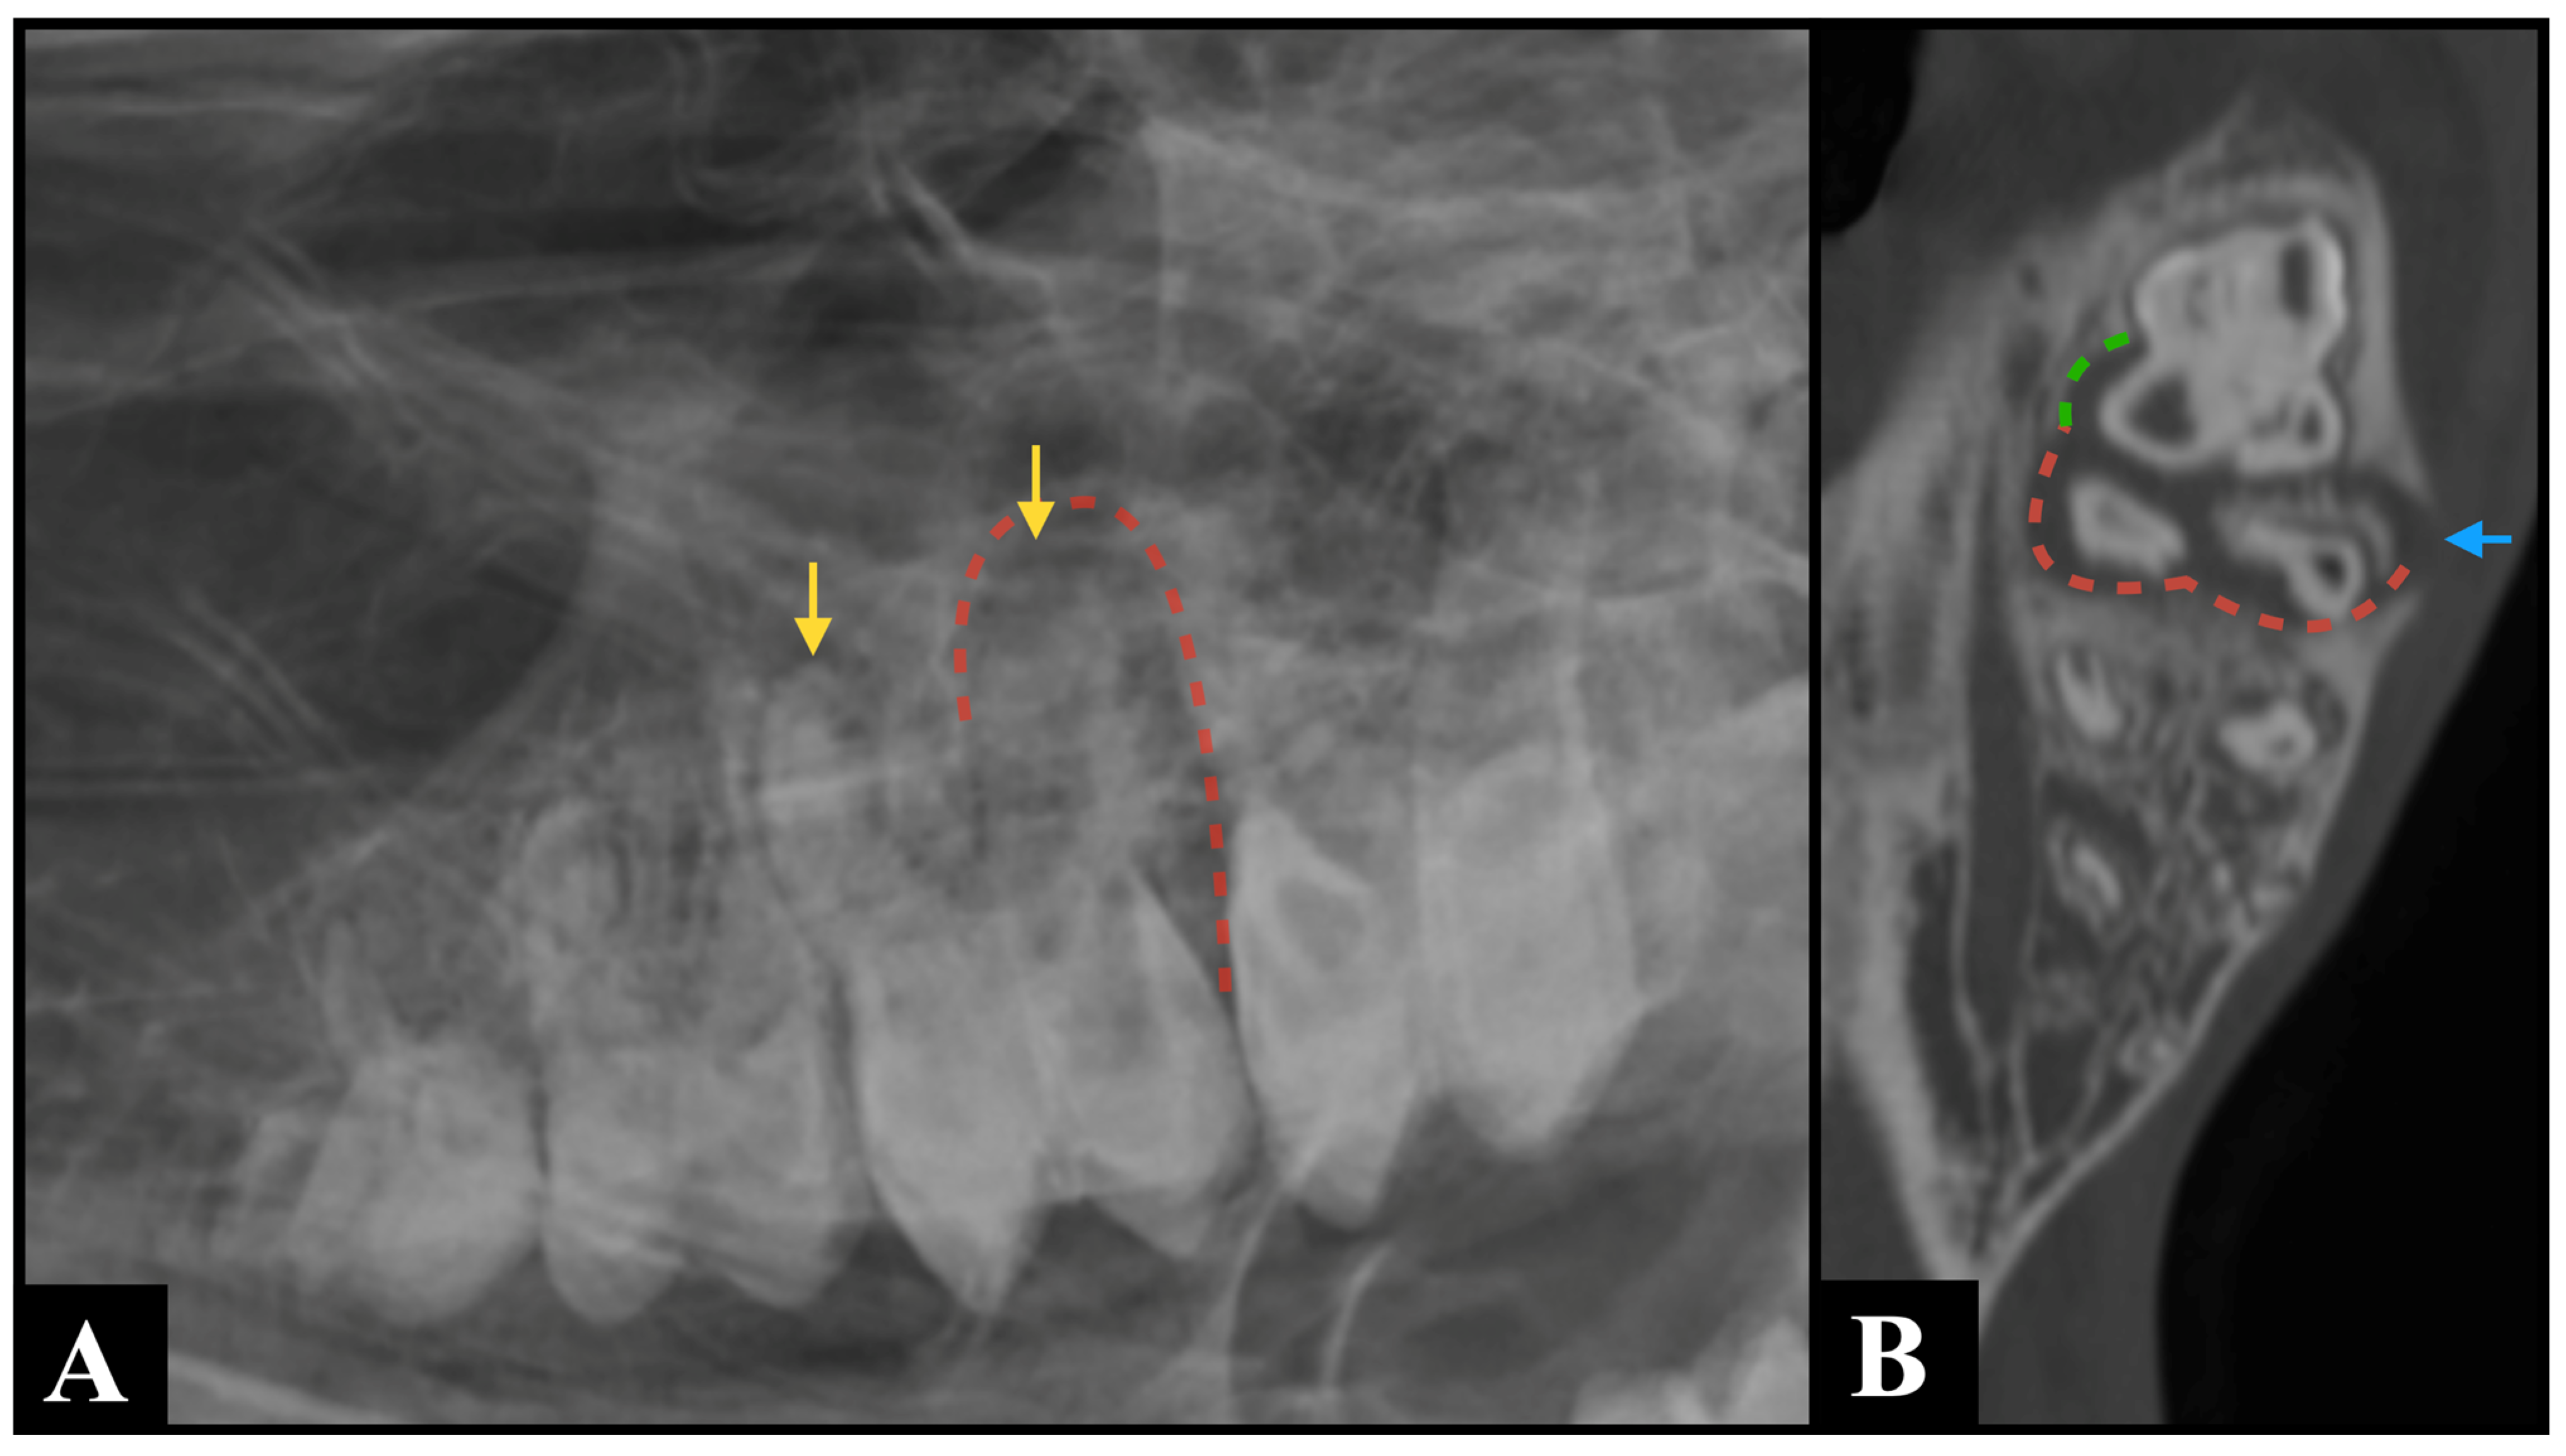

Figure 2.

An R45°V-LDO oblique radiograph (A) and a bone window sagittal plane computed tomography multiplanar reconstruction image (B) demonstrate concordant findings consistent with periapical infection of Triadan 309, characterized by marked widening of the periodontal ligament space (yellow dotted arrow) and sclerosis of the neighboring alveolar bone (blue arrows). However, CT additionally revealed multiple gas foci within the pulp system of this tooth (red arrows)—a finding that was not detectable on the radiographic projection.